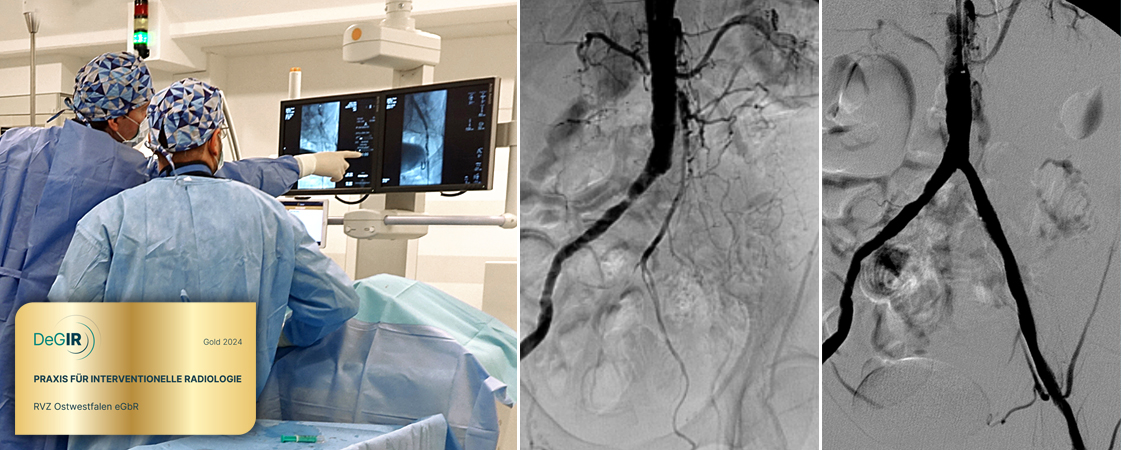

Im Kompetenzzentrum Gefäßmedizin im RVZ Minden werden viele Spezialverfahren wie Ballonerweiterung, Stenteinlage, Thrombusauflösung und Thrombusabsaugung durchgeführt. Nahezu alle Eingriffe können in der Regel ambulant vorgenommen werden – dies ist gerade für ältere Menschen von Vorteil, da so Behandlungen mit Narkose sowie Operationen und Krankenhausaufenthalte vermieden werden können. Lediglich eine ärztlich überwachte Erholung in unserer Tagesklinik für einige Stunden nach dem Minimaleingriff ist notwendig.

DeGIR-zertifizierte Praxis

Das RVZ ist seit Jahren mehrfach von der Deutschen Gesellschaft für Interventionelle Radiologie und minimal-invasive Therapie (DeGIR) als Zentrum für minimal-invasive Gefäßmedizin und Therapien zertifiziert. Weiterhin wurde unsere Praxis für das Jahr 2024 als „DeGIR-Praxis für Interventionelle Radiologie“ mit Gold ausgezeichnet (min. 500 Interventionen).